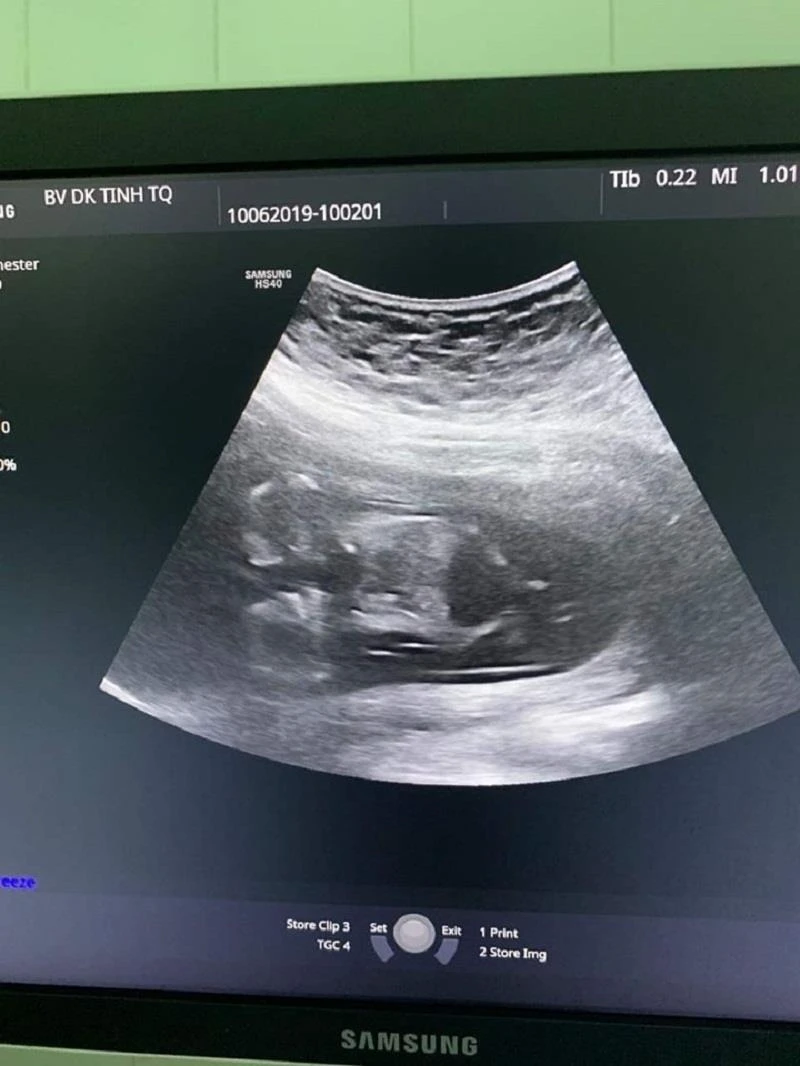

Theo Ths.BS Dương Văn Chương, khoa Phụ Sản, BVĐK tỉnh Tuyên Quang, người trực tiếp thăm khám cho thai phụ Trần Thị Thu P (21 tuổi, huyện Yên Sơn, Tuyên Quang), sản phụ P. mang thai lần đầu, có thai tự nhiên. Kết quả khám thai cho thấy sản phụ mang song thai tuần thứ 12. Điều đặc biệt là 2 thai dính nhau từ phần phần ngực xuống đến phần bụng, có chung một quả tim và cả 2 thai đều có tăng khoảng sáng sau gáy (2,5mm và 8,0mm), dấu hiệu sớm của hội chứng down.

Kết quả siêu âm ở tuần thứ 12 của thai phụ P